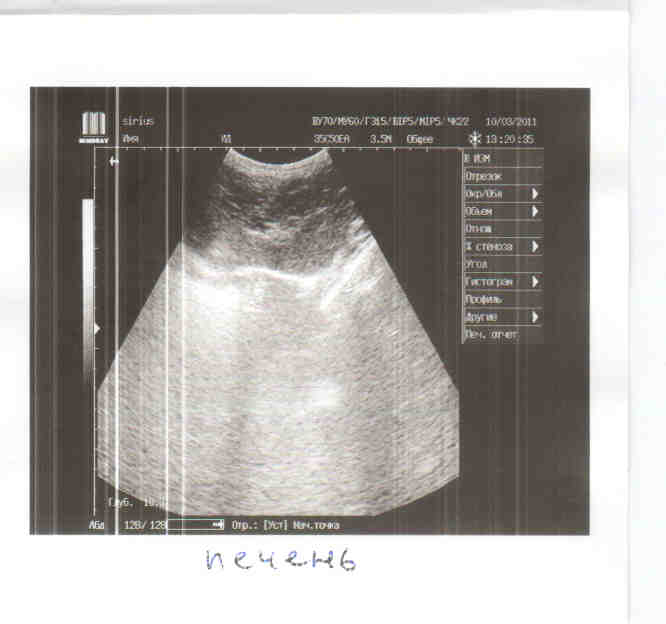

Мне нужна финансовая помощь, конечно большая часть с меня, но все я не потяну сразу. Выкладываю лист назначений, еще не посчитан стационар, т.к. неизвестно как пройдет операция. По состоянию кошка в норме, температура нормальная, почки в норме, а вот с печень небольшие проблемы, нужно будет ее поддержать.